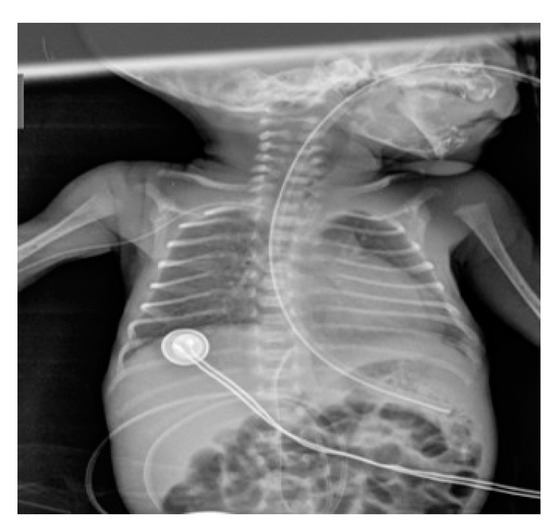

Conventional Radiology Evaluation of Neonatal Intravascular Devices (NIVDs): A Case Series

3. Results